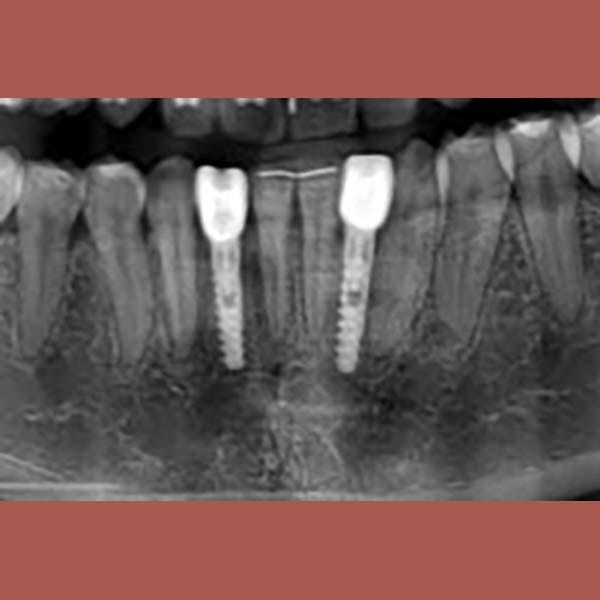

عانت هذه السيدة من وجود عضة عميقة أمامية و غياب خلقي لسنين أماميين سفليين ،بالإضافة لتراكب و عدم ارتصاف الأسنان الأمامية العلوية بشكل جيد – تم فتح مسافة كافية لوضع غرستين سنيتين و تم تصخيح العضة العميقة تقويمياً